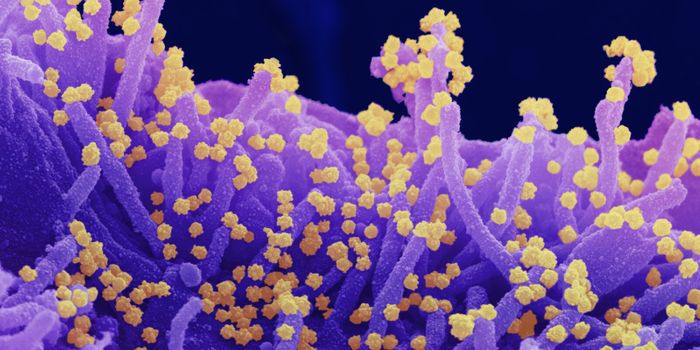

APR 04, 2022Cell & Molecular BiologyAbout 1.5 million new HIV infections are thought to have occurred last year, and while COVID-19 has dominated concerns a ...

FEB 21, 2022Cell & Molecular BiologyTwo people have been cured of HIV, and now, a US woman joins them. In this third case, stem cell transplants were being ...

NOV 22, 2021MicrobiologyThough treatments are available, there is no cure or vaccine from HIV, which impacts about 38 million people worldwide. ...

SEP 06, 2021MicrobiologyHIV vaccines have remained elusive in part because the virus has a powerful ability to mutate, and there are so many str ...

JUN 24, 2021ImmunologyA new study has revealed how stem cells can be used to amplify immune responses to HIV, the virus that causes AIDS. The ...